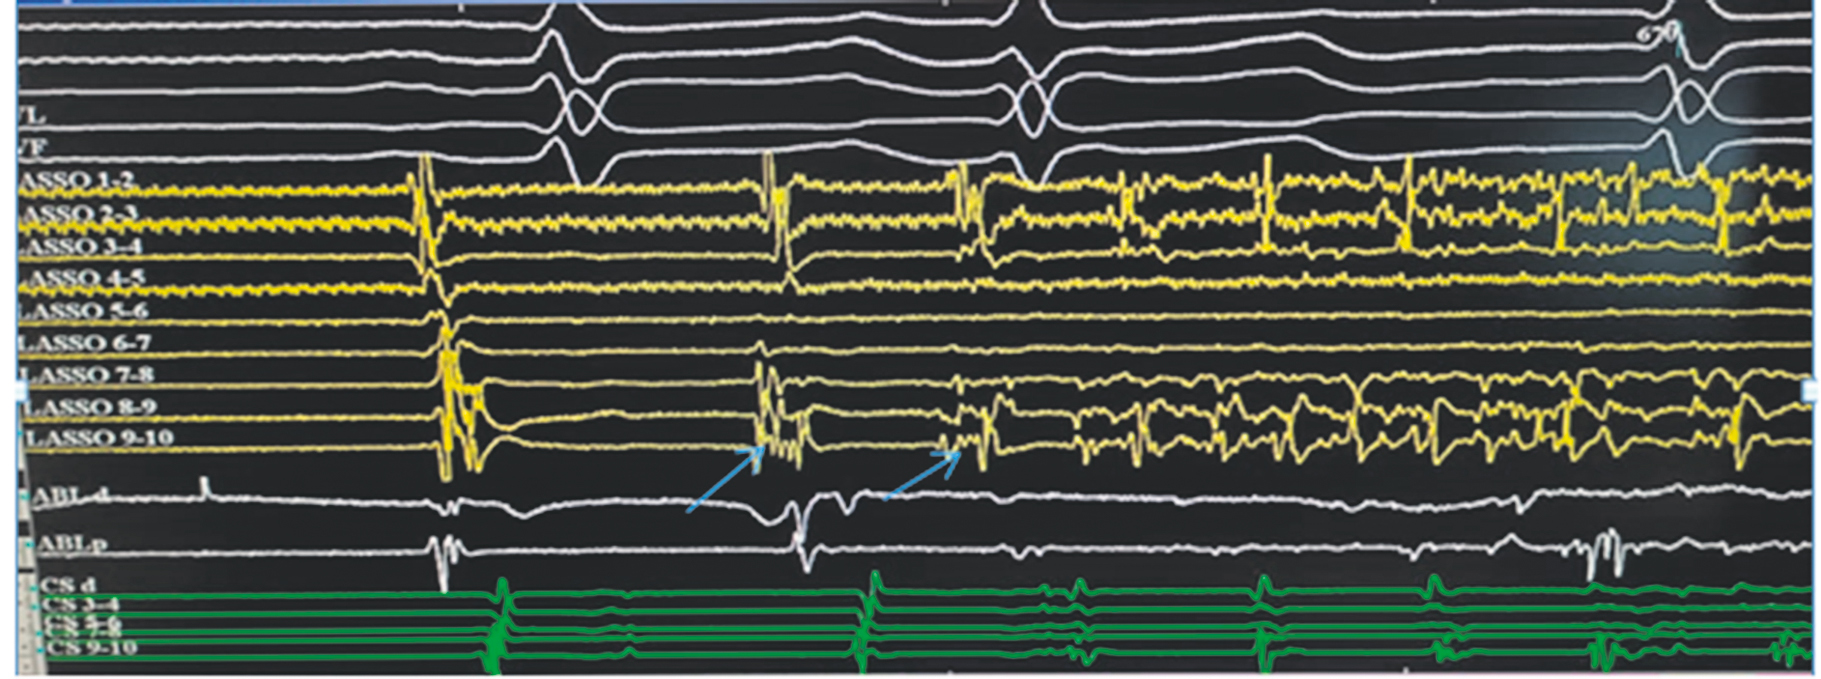

Fig. 3. Amplitude map and recording of the electrocardiogram and endograms of the patient after the labyrinth-3 operation. Top–down: amplitude map of the patient, standard electrocardiogram leads, and signals from the multipole circular electrode (yellow) on the posterior wall of the left atrium, where the arrows indicate the activity from the anastomosis on the left, signals from the ablation electrode (white), and signals from the multipole electrode in the coronary sinus (green). Isolation of the posterior wall was achieved, the dissociation of arrhythmic activity corresponded to data from the Lasso catheter, and flutter persists, and sinus rhythm exists along the electrode from the coronary sinus (also the arrowhead is the lower horizontal arrow on the recording from the coronary sinus). The EPT system “Claris” (Abbott, USA) was used. The recording speed was 200 mm/s

Рис. 3. Амплитудная карта и запись электрокардиограммы и эндограмм пациента после операции лабиринт-3. Сверху вниз: амплитудная карта пациента, стандартные отведения ЭКГ, сигналы с многополюсного циркулярного электрода (желтые) на задней стенке левого предсердия — стрелками указана активность с соустья слева, сигналы с аблационного электрода (белые), сигналы с многополюсного электрода в коронарном синусе (зеленые). Изоляция задней стенки достигнута, диссоциация аритмической активности — по данным с катетера «Lasso», сохраняется трепетание, при этом по электроду из коронарного синуса — синусовый ритм (также стрелка-указатель — нижняя горизонтальная стрелка на записи с коронарного синуса). ЭФИ-система «Claris» (Abbot, США). Скорость записи 200 мм/с